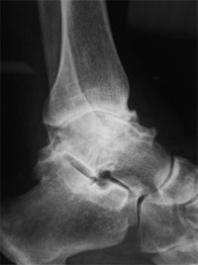

OA skočnog zgloba ( slika 13. i 14. ) je bolno stanje koje otežava aktivnosti svakodnevnog života, u prvom redu hodanje. Skočni zglobovi su strukture koje ljudskom tijelu omogućavanju hodanje, trčanje i skakanje

Slika 13.

Slika 14.

&RTG snimka – na takvoj snimci se može vidjeti prisutnost koštanih izdanaka, gubitak hrskavice kao i fizičke promjene na kostima